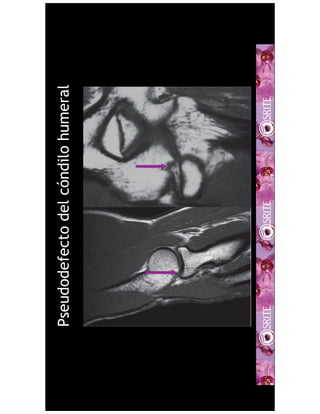

This medical document discusses pseudodefects of the humeral condyle and trochlear crest seen on MRI scans of the elbow. Specifically, it references a 1995 article in the American Journal of Roentgenology by Rosenberg, Beltran, and Broker that describes pseudodefects of the humeral condyle and trochlear crest seen on sagittal plane MRI images of the elbow.